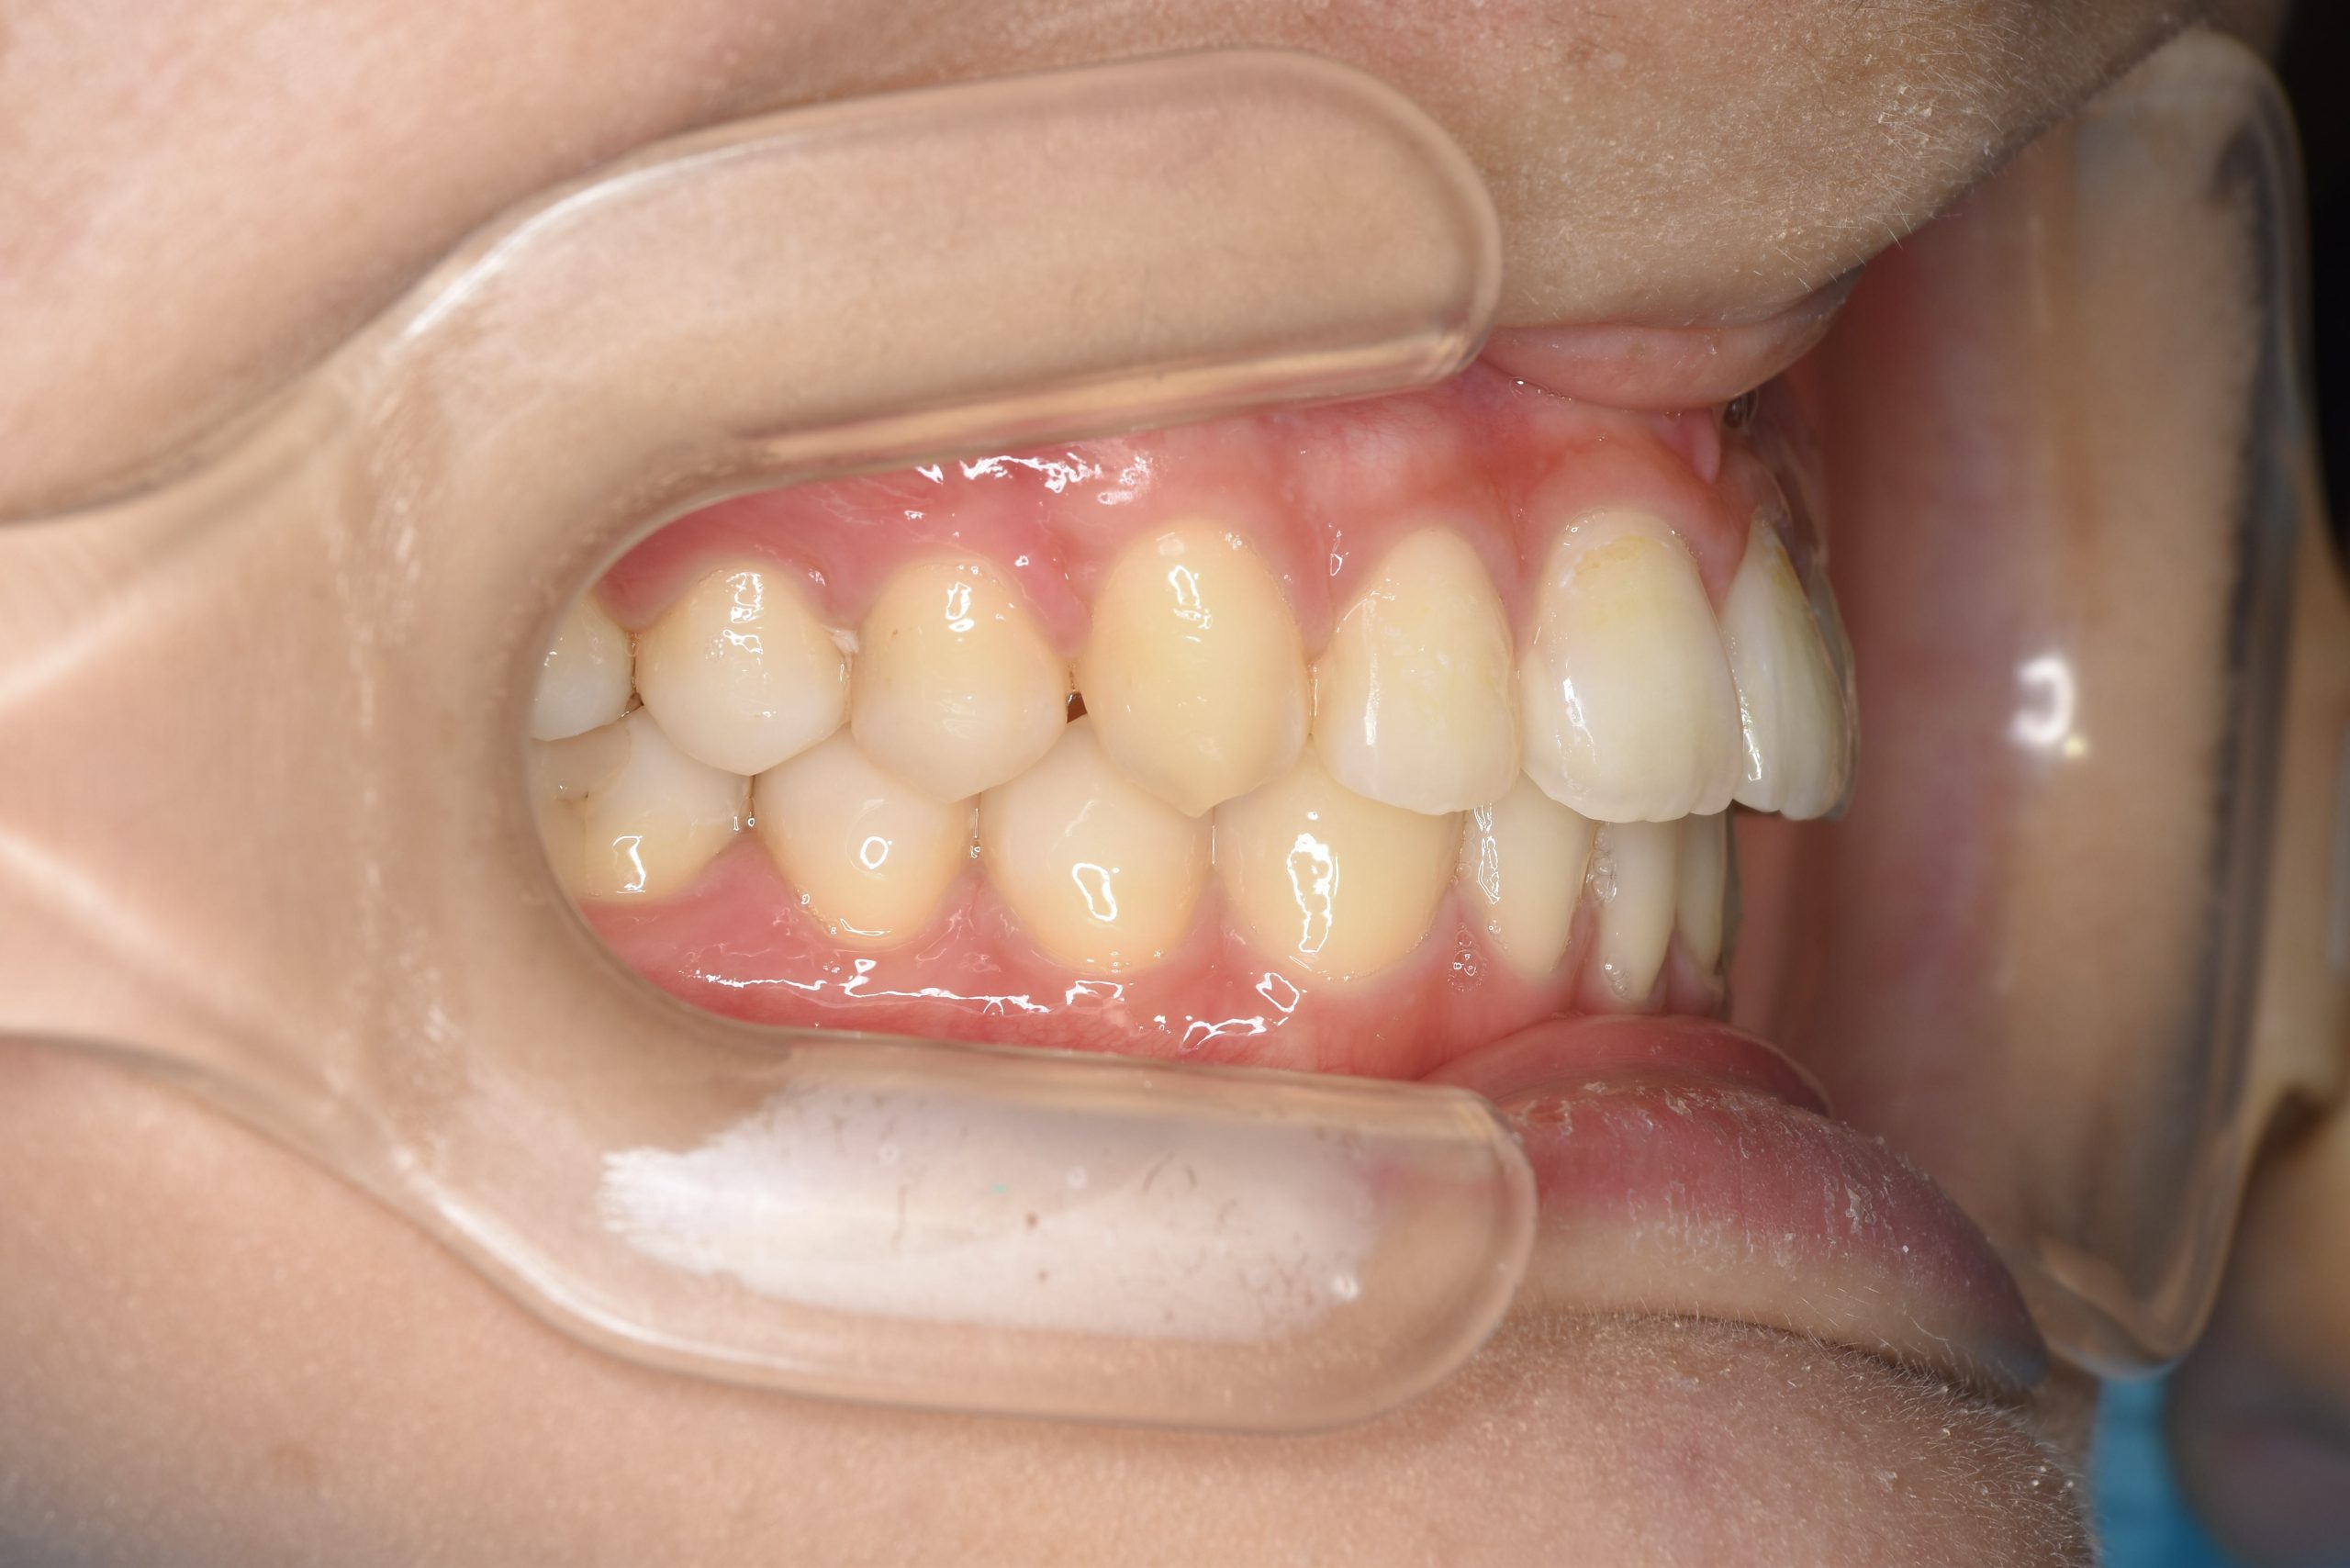

アフター

ワイヤー矯正治療|症例_009

主訴 出っ歯

施術内容 MSEと下顎リンガルアーチを用いて上下顎骨を拡大した。

その後マルチブラケット装置とミニインプラントを用いて非抜歯で歯牙を配列した。

下顎前歯が1本先天性欠損であったが、良好な咬合を獲得した。口元の突出感と鼻閉症状は改善された。

治癒期間 2年3ヶ月間